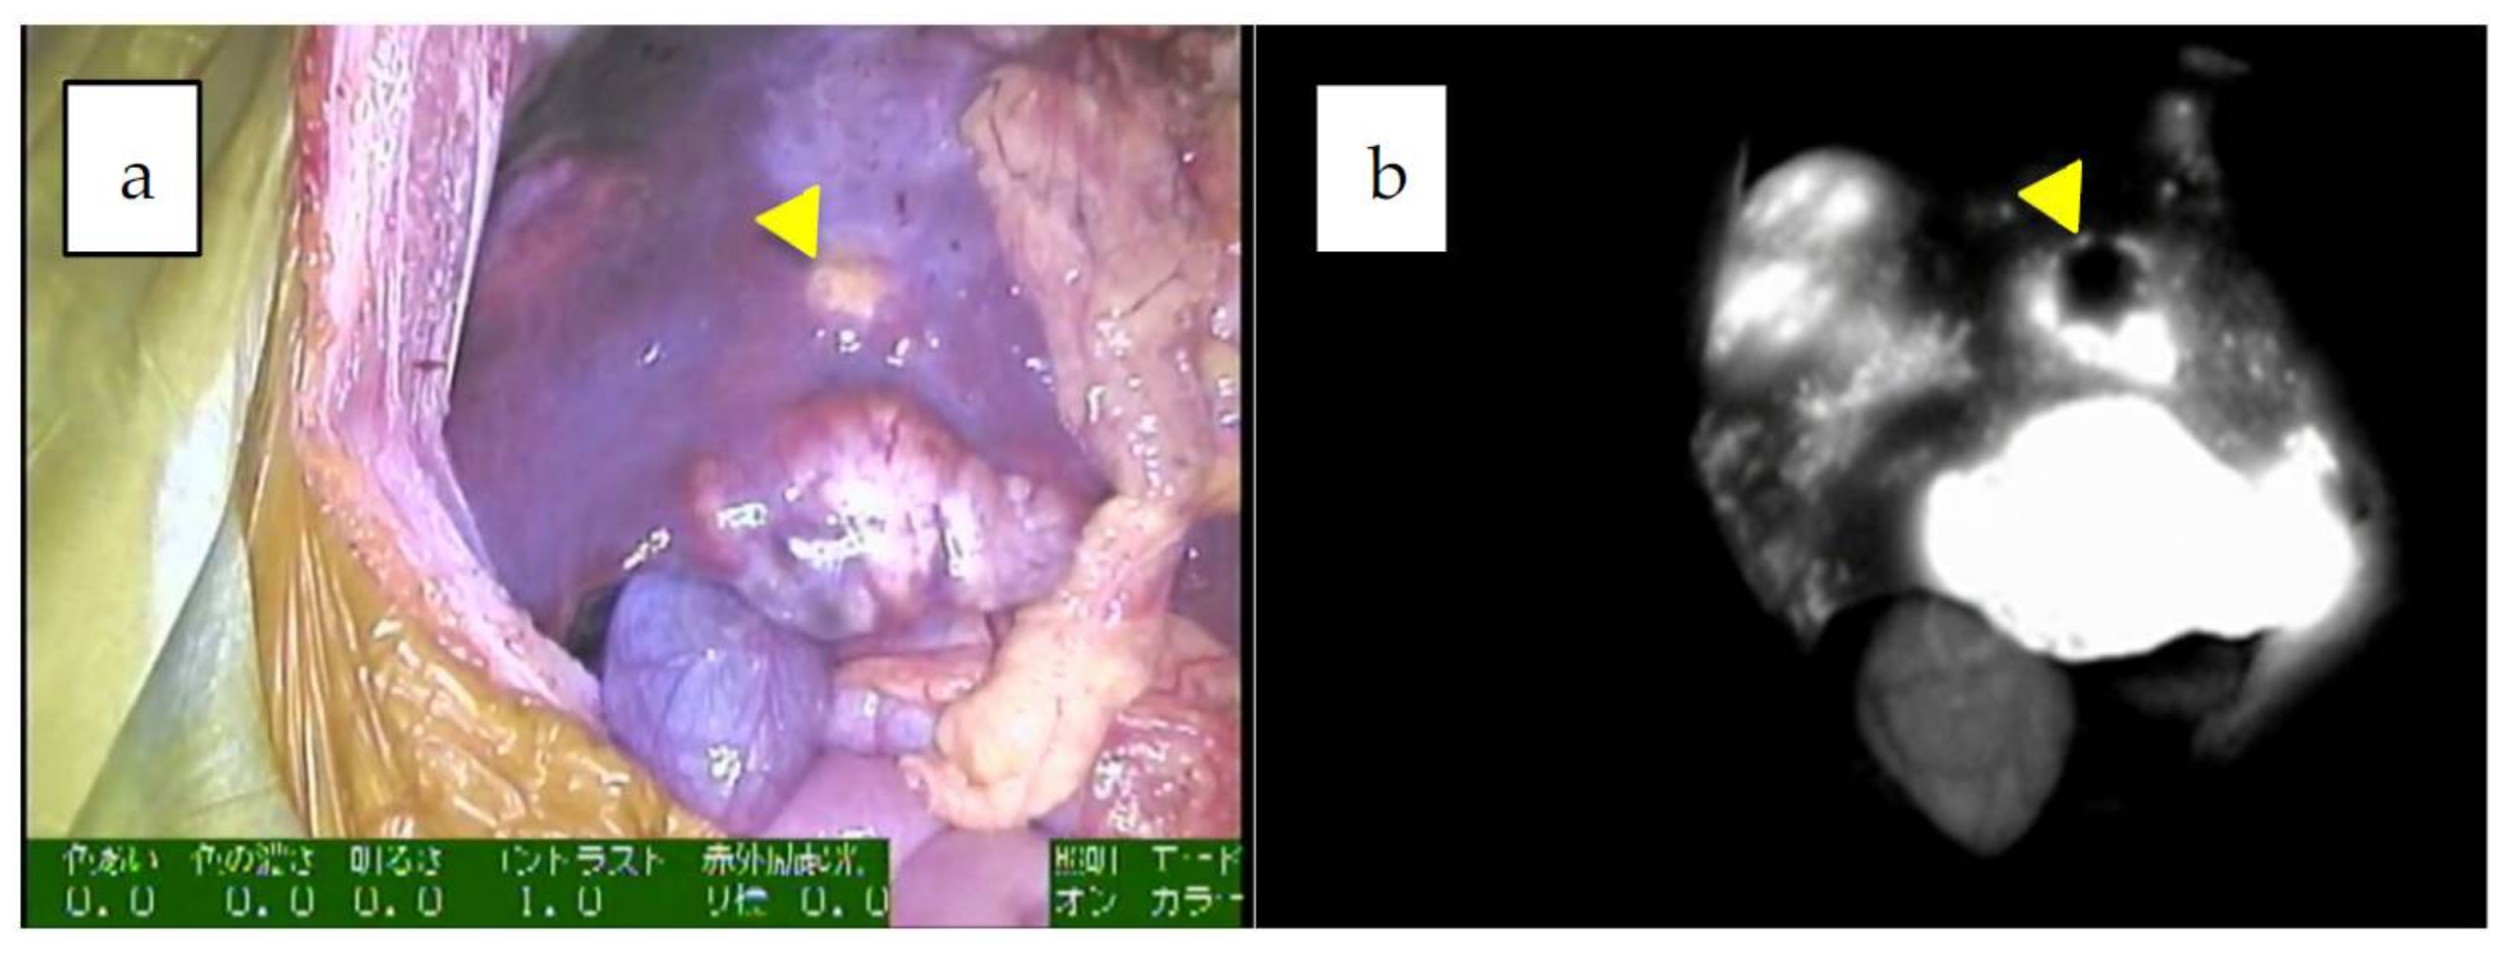

| 5 | 5 | 4y/M | PDE neo system | LDLT 2 | combined fetal and embryonal subtype, post-chemotherapy | uneven | 90 mm | 42591 | identification, surgical margin, newly detected tumors, 19 m |

| 8 | 8 | 14y/M | PDE neo system | partial resection (recurrences in the transplanted liver) | wholly epithelial type and fetal subtype | diffuse | 8 mm | 69 | identification, surgical margin, newly detected tumors |

| 9 | 8 | 14y/M | PDE neo system | LDLT 2 | wholly epithelial type and fetal subtype | diffuse | 8 mm | 394 | identification, surgical margin, 34 m |